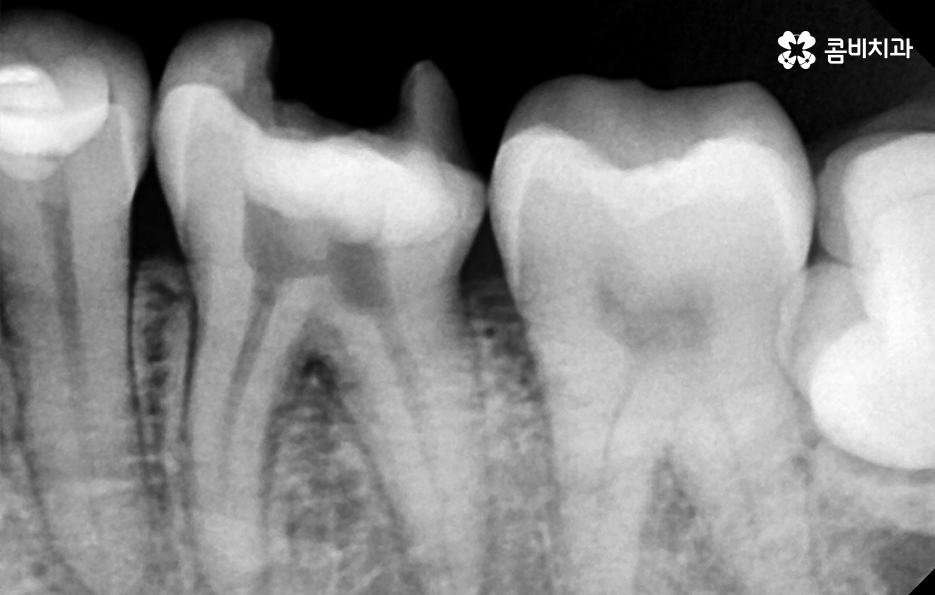

사랑니는 치아 중에서도 가장 마지막에 맹출이 되며 현대인들은 턱뼈가 좁아지는 추세이기 때문에 마지막에 자라는 사랑니는 위 케이스처럼 윗니의 경우 어금니의 높이 보다 다소 낮게 자라는 경우가 많고 아랫니의 경우 매복되어 있거나 누워서 자라는 사랑니의 형태로 자라는 경우가 많이 있는데요. 이러한 사랑니의 형태로 인해 어금니와 사랑니 사이에 이물질이 끼기 쉽고 칫솔질이 잘 닿지 않기 때문에 충치 뿐 아니라 잇몸 염증이 발생되는 경우가 많으며 사랑니 어금니 통증의 원인이 주변의 세균 증가로 인해 충치로 이가 썩은 경우부터 잇몸이 자주 붓고 염증이 심해지면서 통증을 느끼는 경우가 40,50대 이후에 흔하게 발생되는 사랑니와 인접한 어금니의 문제로 볼 수 있어요

일반적으로 30대 이후에는 치주질환이 급증하게 되는데 40,50대 이후에는 잇몸이 점점 내려 앉게 되고 부분적으로 맹출된 사랑니 주변 잇몸 역시도 조금씩 내려앉는 경우가 많이 있는데요. 사랑니 사진을 보시면 아시겠지만 일반적인 치아의 높낮이와는 달리 사랑니가 어금니의 뿌리 부분 정도 높이에 자리하고 있는 것을 볼 수 있어요.